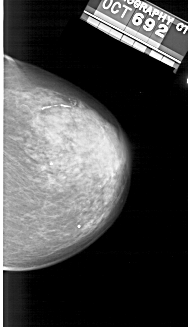

A_1393_1.LEFT_MLO

LEFT_MLO LINES 5491 PIXELS_PER_LINE 2836 BITS_PER_PIXEL 12 RESOLUTION 43.5 OVERLAY